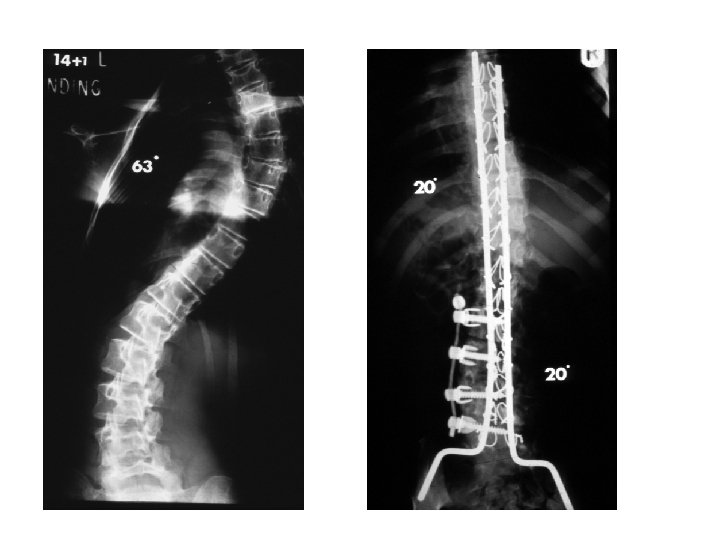

Idiopathic Scoliosis SURGICAL CORRECTION GOALS u. Reduce the magnitude of the curve u. Obtain fusion to prevent progression u. Create a well-balanced spine

Idiopathic Scoliosis • • • SURGICAL CORRECTION INDICATIONS Curves over 45 degrees Trunk deformity(rotation) Trunk balance Progressive curves despite bracing Congenital scoliosis Neurologic symptoms

Idiopathic Scoliosis • • GENERAL GUIDELINES FOR TREATMENT OF SCOLIOSIS Under 20 degree’s: observe 20 to 30 degree’s: observe with frequent follow-up; progression then brace 30 to 45 degree’s: brace unless Risser 4/5 then observe 45 plus degree’s: instrumentation

Scoliosis treatment plan Curve Risser Therapy 0 -25 Immature observe 25 -30 immature brace 30 -45 immature brace >45 immature surgery >50 mature surgery

Surgical Treatment for Scoliosis • Curves in growing children greater than 40 º require a spinal fusion (Risser grade 0 to 1 in girls and Risser 2 or 3 in boys) • Skeletally mature patients can be observed until their curves reach 50 º • Posterior spinal fusion is best choice for thoracic curves • Anterior spinal fusion is best treatment for thoracolumbar and lumbar curves

Surgical Treatment for Scoliosis